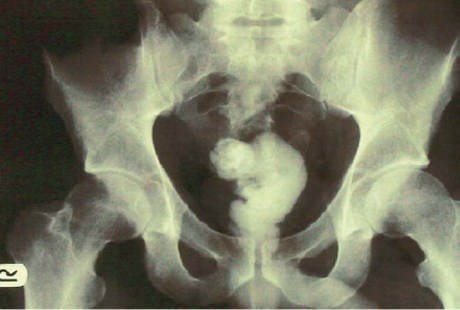

Namun dari hasil radiografi, di dalam perutnya ditemukan bayangan seekor belut. Setelah ditanya-tanya, akhirnya ia mengaku memasukkan seekor belut ke ususnya untuk meredakan sembelit.

Bahkan si belut juga sempat menggigit sebagian usus besar si kakek sehingga dokter menemukan perforasi atau lubang sepanjang 3 cm di dinding atas ususnya. Tak butuh waktu lama, dokter langsung memintanya melakukan tindakan laparotomy untuk mengeluarkan belut sepanjang 50 cm itu. Seminggu kemudian si pasien sudah diperbolehkan pulang.